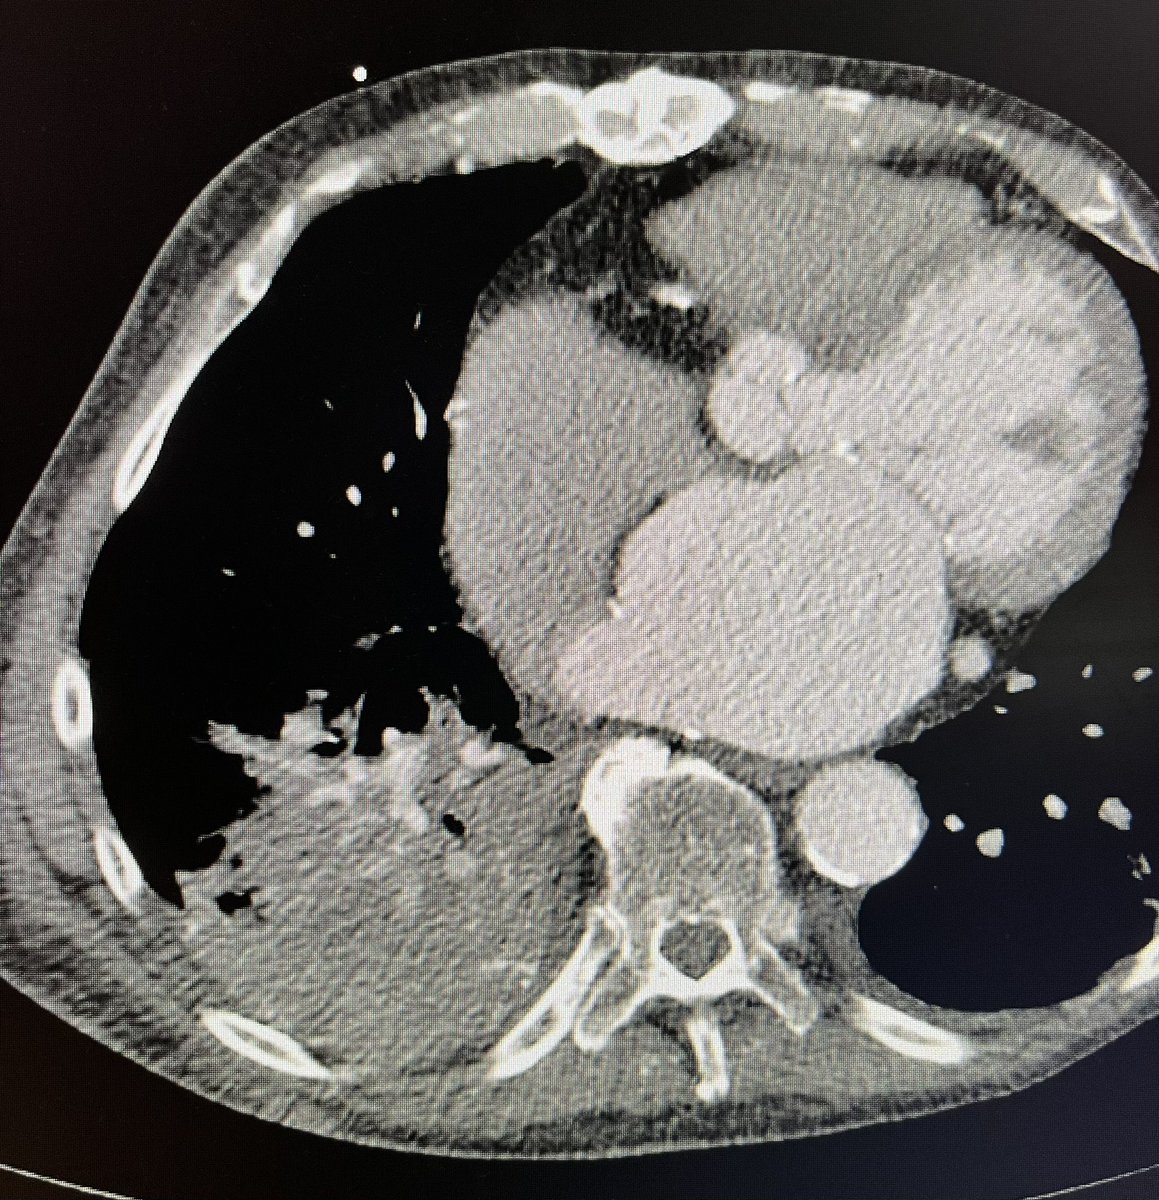

One of the 1st studies in healthcare using @HoloLens 2, supported by @RSNA. #AugmentedReality guidance improves procedure times and radiation dose. Med students also instantly elevated to #IRAD attending level! @dotter_IR @Penn_IR @PigiLab @SIRRFS rdcu.be/b9p98